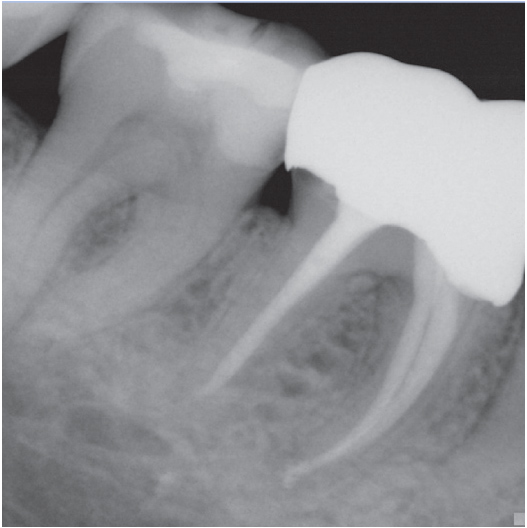

Before

Before Root Canal treatment